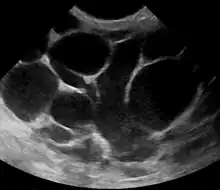

Risk factors include poor latch, cracked nipples, use of a breast pump, and weaning.[1] The bacteria most commonly involved are Staphylococcus and Streptococci.[1] Diagnosis is typically based on symptoms.[2] Ultrasound may be useful for detecting a potential abscess.[1]

The diagnosis of mastitis and breast abscess can usually be made based on a physical examination.[24] The doctor will also take into account the signs and symptoms of the condition.

However, if the doctor is not sure whether the mass is an abscess or a tumor, a breast ultrasound may be performed. The ultrasound provides a clear image of the breast tissue and may be helpful in distinguishing between simple mastitis and abscess or in diagnosing an abscess deep in the breast. The test consists of placing an ultrasound probe over the breast.